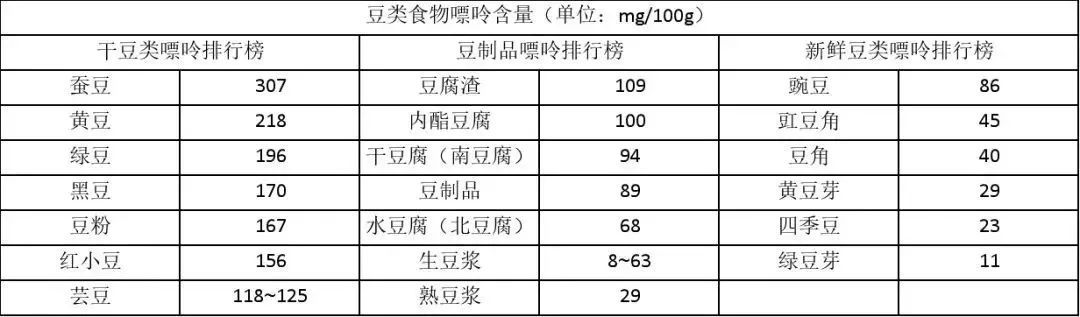

得知陆先生一天吃两碗豌豆后,医生表示新鲜豌豆嘌呤含量达86mg/100g,属于中嘌呤食物,短时间内大量食用也会给尿酸“火上浇油”。

蚕豆、黄豆、绿豆、黑豆等干豆类嘌呤值均超150mg/100g,属于高嘌呤食物(嘌呤含量>150mg/100g);

豆腐、豆浆等豆制品因浸泡、磨浆等工艺,嘌呤流失过半,多数为中低嘌呤食物;

新鲜豆类由于水分较多,多数为低嘌呤食物(新鲜豌豆除外)。